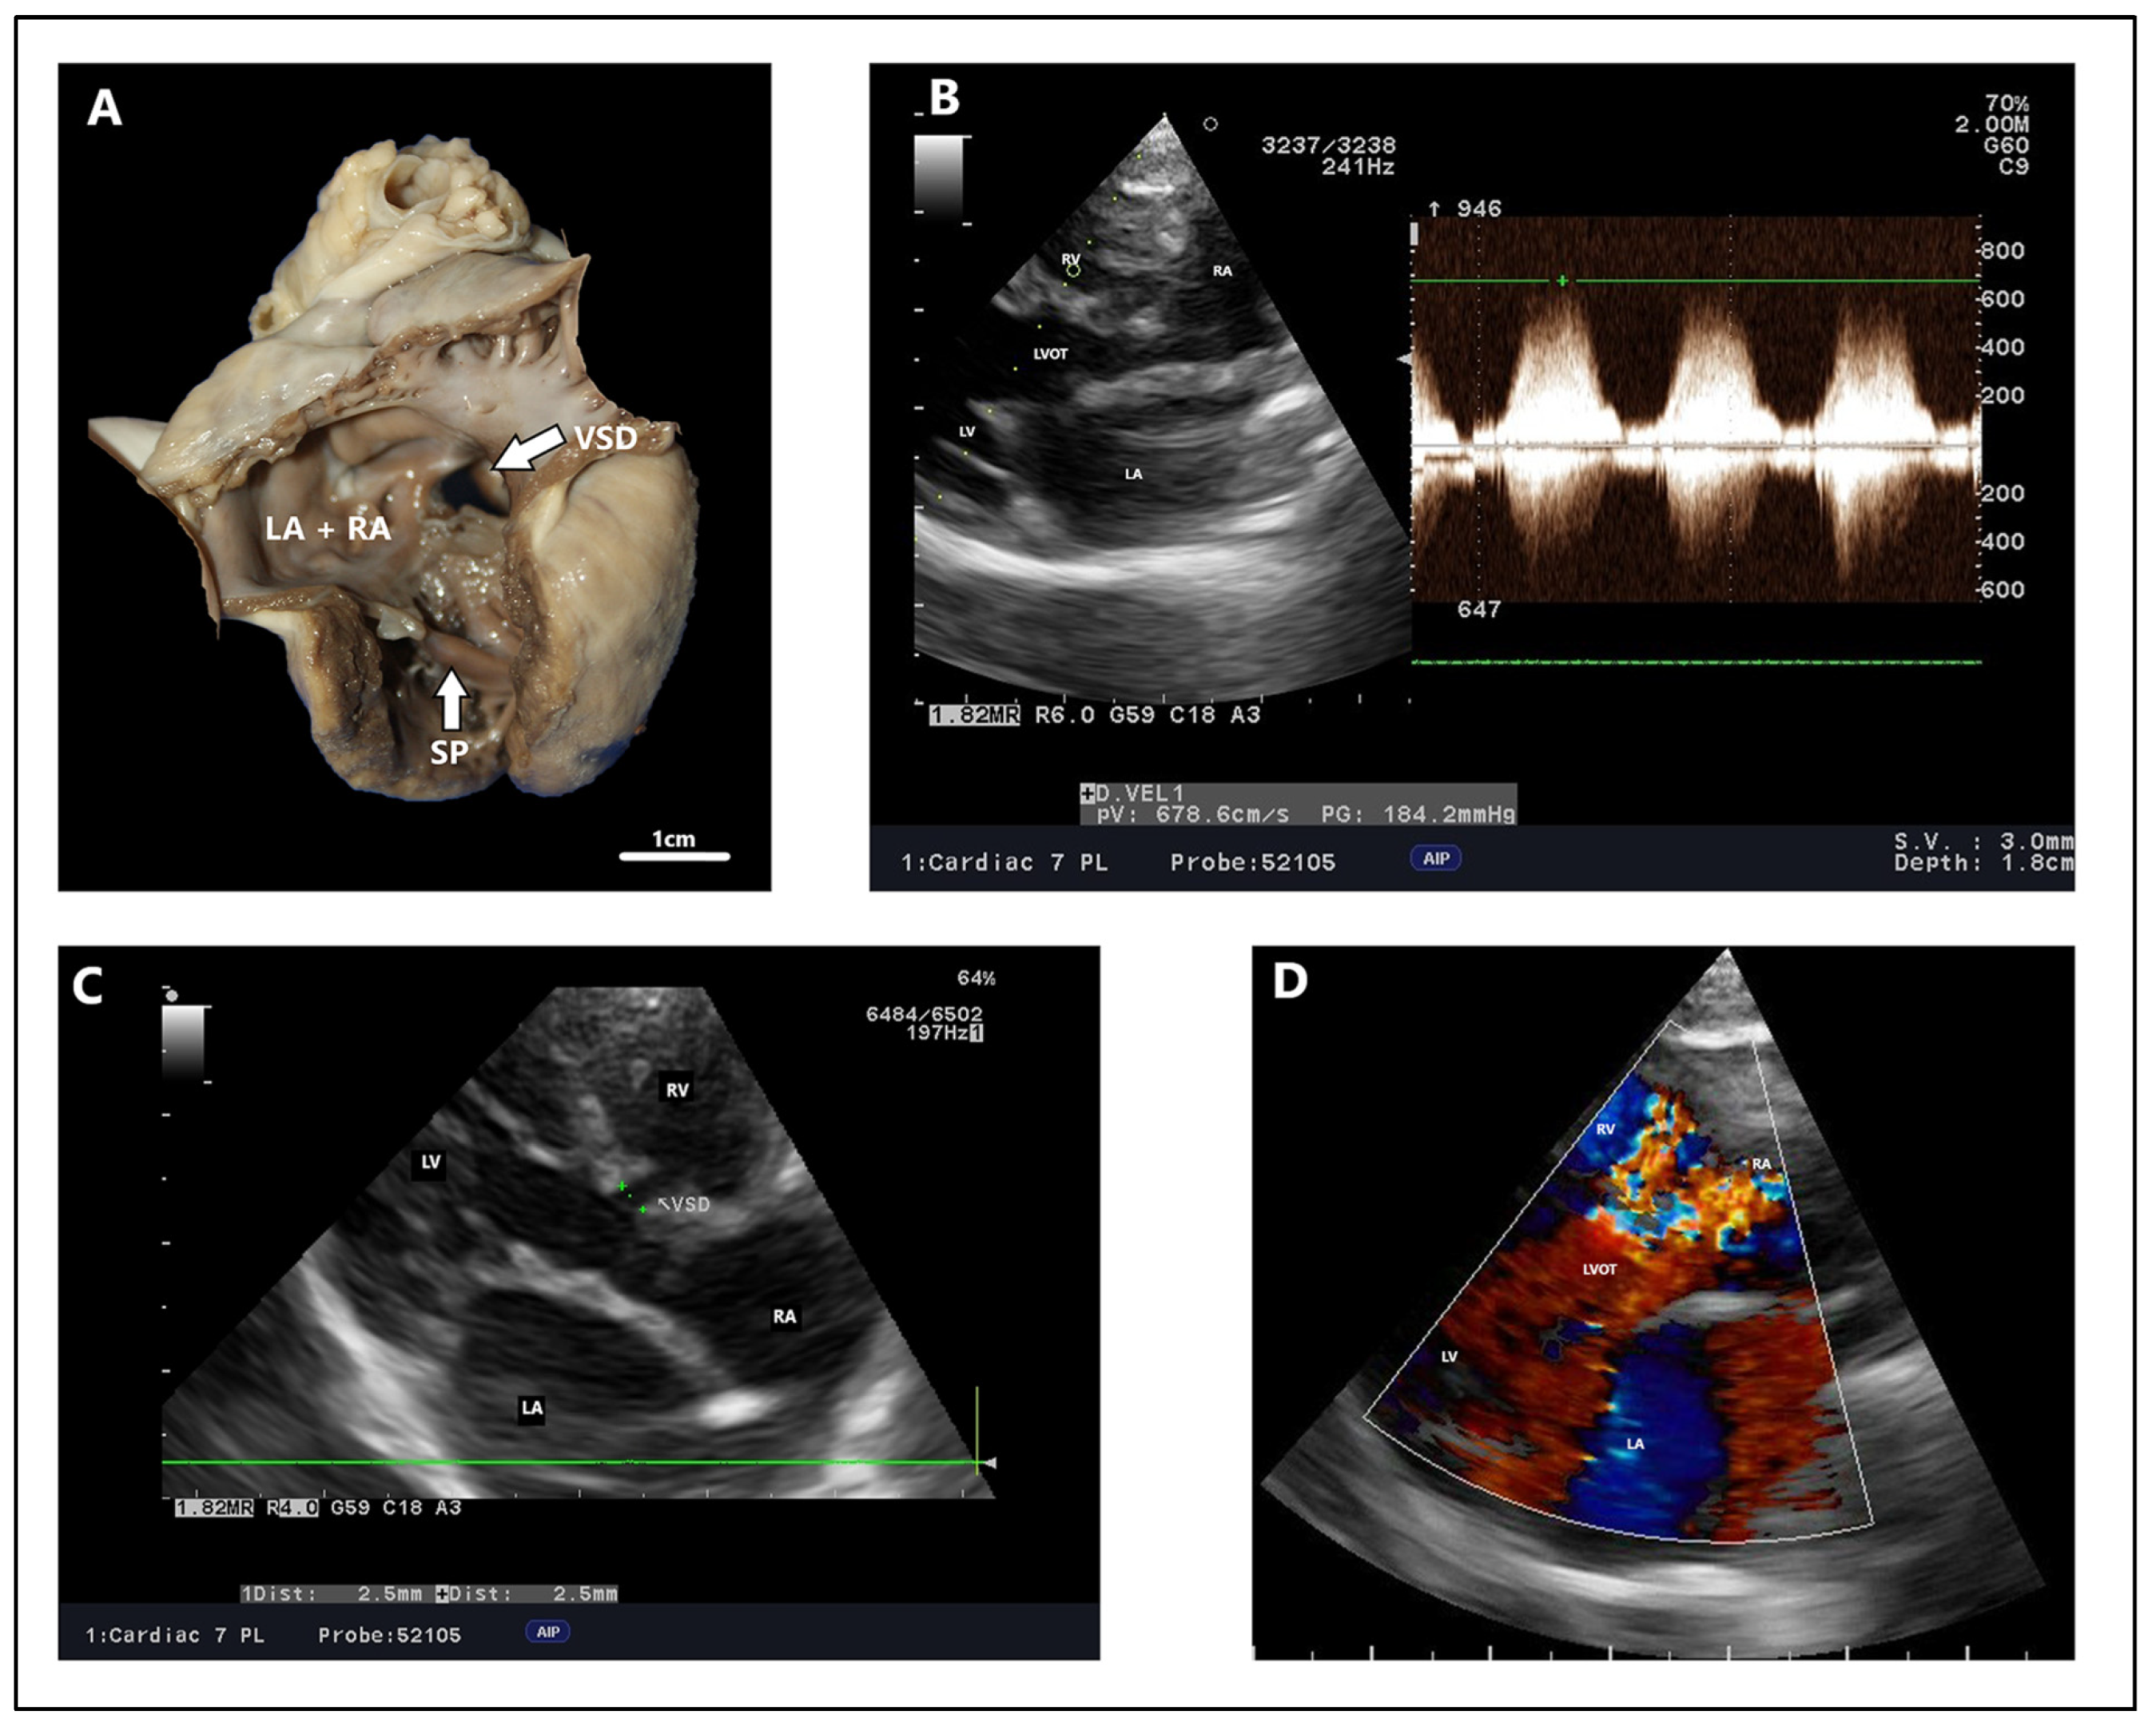

4.2. Echocardiography, Radiography, ECG Findings